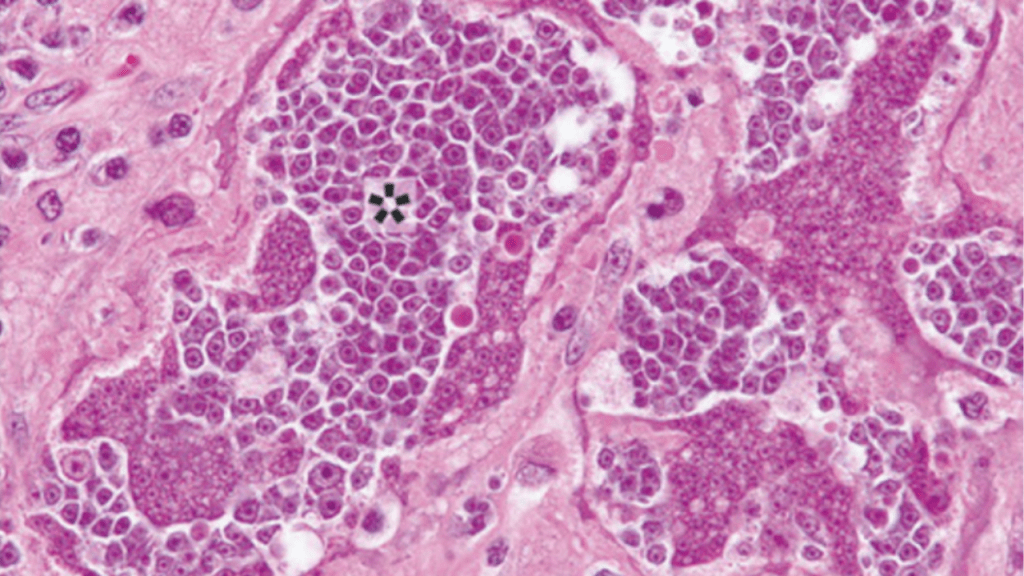

Inicialmente, los médicos asumieron que se trataba de un cáncer humano convencional. Sin embargo, las biopsias mostraron algo inusual: las células tumorales eran mucho más pequeñas de lo esperado y no encajaban del todo con ningún tipo de cáncer conocido.

Ante esta anomalía, el equipo médico recurrió a técnicas avanzadas de análisis genético y molecular. Los resultados fueron sorprendentes. El ADN de las células malignas no coincidía con el del paciente. En cambio, correspondía a Hymenolepis nana, una solitaria enana común en regiones con deficiencias sanitarias.

El estudio concluyó que el parásito había desarrollado un proceso de transformación maligna dentro del cuerpo del huésped. Las células cancerosas del gusano se multiplicaron y se diseminaron, comportándose de manera similar a un cáncer agresivo humano. Este fue el primer caso documentado de un cáncer derivado directamente de un parásito en un ser humano.

Las células del parásito, aun siendo diez veces más pequeñas que las humanas, mostraron características claras de malignidad, como crecimiento descontrolado e invasión de tejidos. El caso reforzó la importancia del sistema inmunológico como una barrera clave frente a procesos de cáncer inusuales.